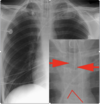

Is this a proper placement of a central line?

* No, the tip (smaller red arrow) is within the right ventricle. Pt will probably experience PVCs. * The catheter tip should lie between the most proximal venous valves of the subclavian or jugular veins and the right atrium.